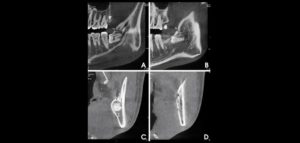

Se sabe que la tomografía computarizada de haz cónico (CBCT) produce exploraciones tridimensionales de la dentición, las estructuras duras maxilofaciales y la relación de las